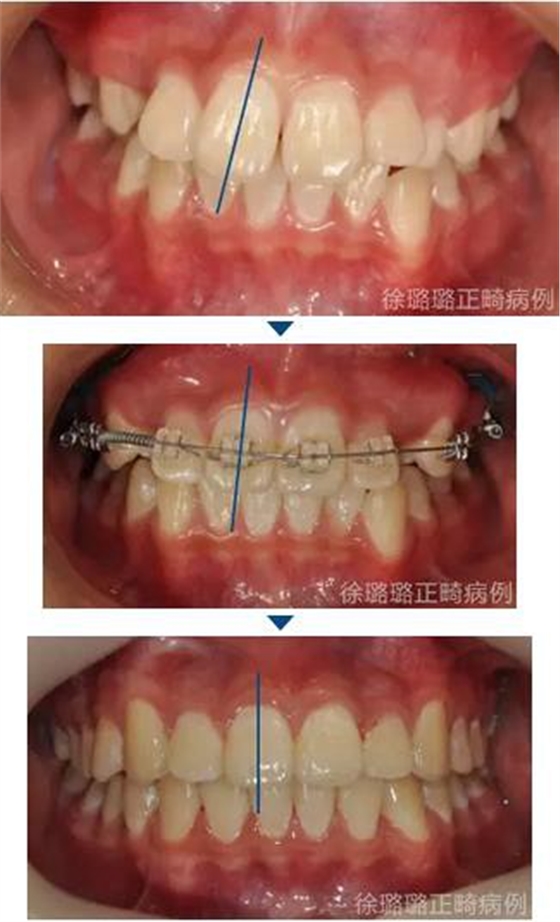

口外特征:正面觀面部左右不對稱(微笑時加重),側(cè)面觀面中部 1/3 略顯凹陷,顳下頜關(guān)節(jié)未及異常。

口內(nèi)特征:恒牙早期,雙側(cè)磨牙關(guān)系為輕度遠(yuǎn)中關(guān)系,前牙深覆牙合 Ⅱ°,深覆蓋 6mm,上下頜牙弓中線不端正,上頜中線右偏 3mm,上頜前牙唇傾,下頜牙列輕度擁擠,右側(cè)上頜間隙不足,左側(cè)乳尖牙滯留,上頜左側(cè)乳尖牙對刃牙合,上下頜牙弓形態(tài)不對稱。

面部分析:面部左右對稱、和諧;凹面型得到改善。

咬合分析:建立了雙側(cè)磨牙及尖牙 I 類關(guān)系;前牙覆牙合、覆蓋關(guān)系正常;上下中線基本與面中線一致。